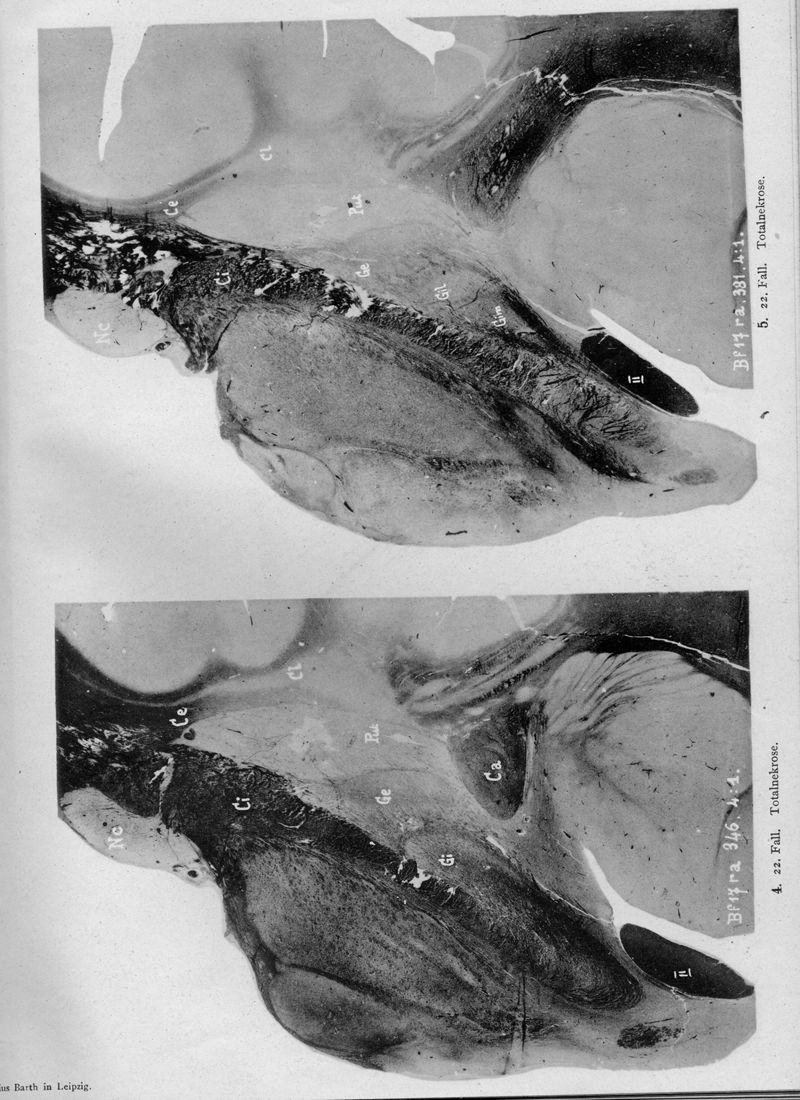

VOGT, Cécile / VOGT, O.

In : Journal für Psychologie und Neurologie,

1920, Vol. 25, pp. 627-846